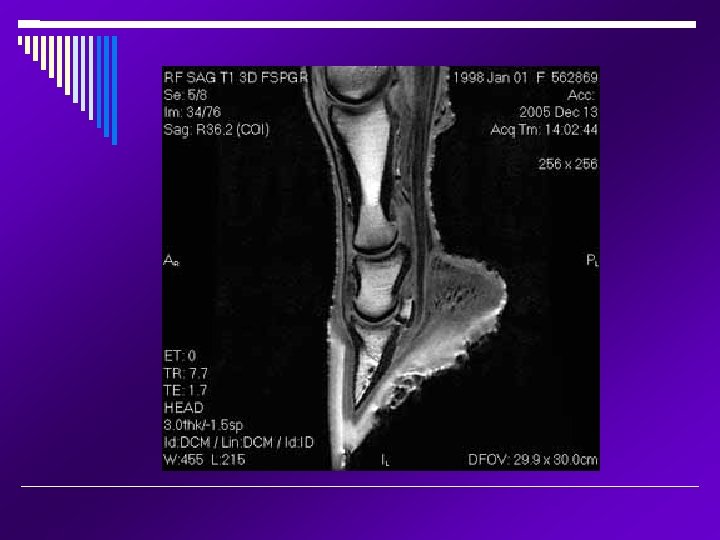

MRI Magnetic Resonance Imaging; the area being imaged is placed within a strong magnetic field and stimulated by radio-frequency pulses. These radio-frequency signals are collected analyzed by computers to form the image. Very, very costly and not widely available Anesthesia is required MRI tend to be superior to CT for soft tissue imaging The head, cervical spinal cord and lower legs can be imaged in an adult animal Precise and focal imaging tool that produces images of all tissue types; bone, tendons, ligaments, and fluid. Mainly utilized in equine lameness.